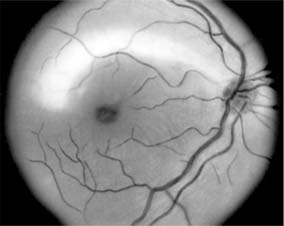

Figure 14-8

Figure 14-8: Mild disk swelling in demyelinative papillitis, with disk leakage on fluorescein angiography.